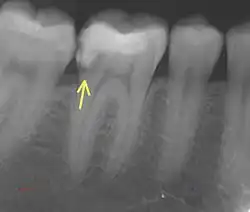

Er bezeichnet eine erneute Kariesbildung an einer bereits behandelten kariösen Stelle, beispielsweise an einem überstehenden, ungenügend dichten oder schadhaften Füllungs- oder Kronenrand.